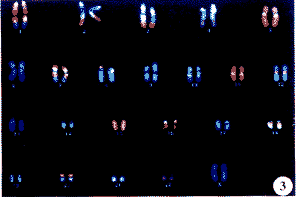

图3 患儿染色体RxFISH

Fig 3 The result of RxFISH

细胞遗传学G显带分析显示:患儿父母为正常核型,分别为46,XY和46,XX。患儿核型为46,XX,9p+,即每个分裂相均有一条9号染色体短臂延长,增加了一条额外深带(图1a)。为探明额外染色体片段的来源,采用9号染色体涂染探针进行染色体涂染,结果显示两条9号染色体(包括短臂额外片段)被均匀涂染(图1b,图2),其它染色体未见杂交信号,因此除外了存在染色体易位或插入的可能性,提示有染色体内重复。CGH证实该额外片段为9号短臂完全重复(图1c)。RxFISH的结果将患儿的核型准确地描述为46,XX,dup 9p(p11→p24∷p24→qter)(图1d、图3)。